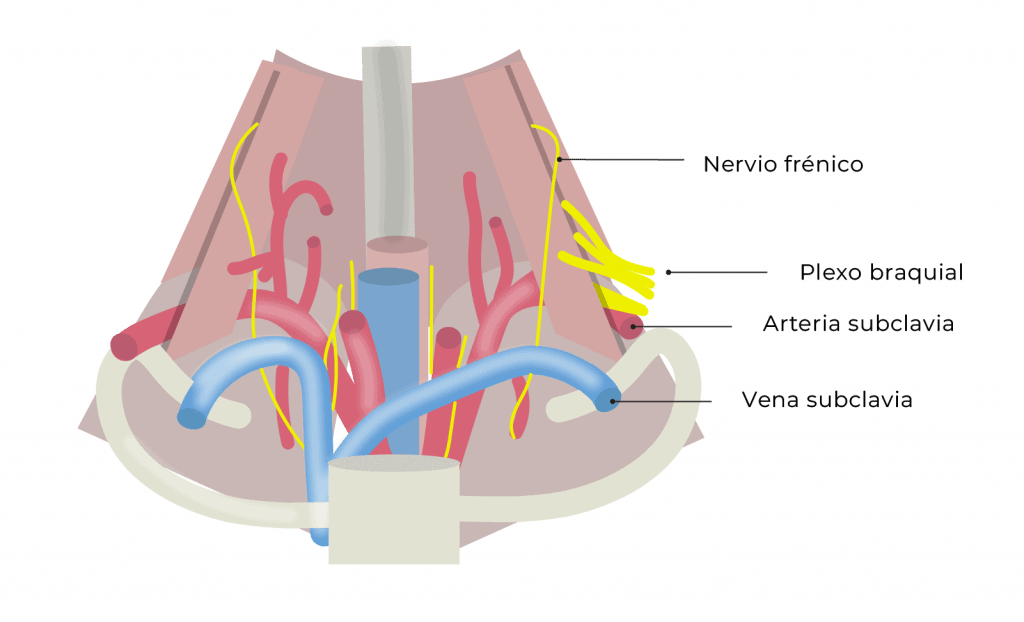

Al llegar a la base del cuello, por debajo del punto medio de la clavícula, todos los componentes del plexo entran en contacto con la arteria subclavia. Es en este sitio donde se realiza el abordaje supraclavicular.

Por otra parte, los troncos superior y medio dentro de la fascia que envuelve al plexo se colocan en la cara superoexterna de la arteria, junto con el nervio supraescapular.

Además, las raíces C8 y T1 (o el tronco inferior, dependiendo de la estructura y variabilidad anatómica de cada persona), se colocan en su cara interior (correspondiendo con el denominado “Corner Pocket”).

La arteria subclavia asciende desde el mediastino superior por la cúpula pleural y luego cursa sobre la cara superior de la primera costilla, entre las inserciones de los músculos escalenos anterior y medio, por debajo del punto medio de la clavícula.

La inserción del músculo escaleno anterior separa la arteria de la vena subclavia y es de los pocos sitios anatómicos en los cuales una arteria y su vena acompañante se encuentran separadas.